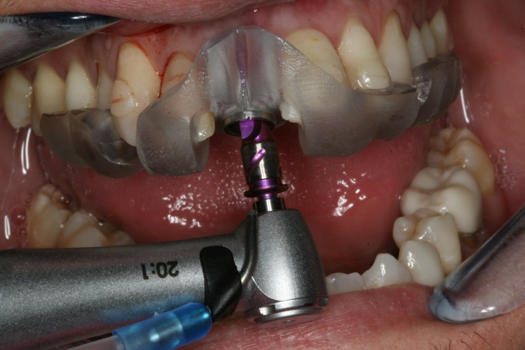

Fig 18. Final implant drill to depth.

Figure 18

The decision was to develop a surgical guide, place the implant, and fabricate a screw-retained one-piece non-engaging abutment with a slender emergence profile and a polymethyl methacrylate (PMMA) provisional. Ten days after the trauma, the patient was seen in the dental office for the placement of the dental implant. On the day of surgery, a 3D-printed surgical guide was used, developed from the CBCT radiograph and the digitized impressions (Figure 17 and Figure 18).

On the day of surgery, the plan was to extract teeth Nos. 21, 23, 24, 25, and 26, place 3.0 x 13-mm implants in the anterior region due to limited spacing, and place a 4.1 x 10-mm implant in the No. 21 extraction site. Before the extractions were performed, the No. 23 pontic was sectioned from the existing 2-unit cantilevered bridge utilizing ceramic and metal high speed rotary cutting burs ZR 6881 and H34L (Komet-USA), respectively. After removal of the pontic and extractions, the surgical guide was verified to be seating positively (Figure 36 through Figure 38). Surgical guide protocol was followed, and all implants were successfully placed and torqued to a value of greater than 35 Ncm (Figure 39 and Figure 40). All implants were placed without flapping, with the exception of No. 23. The flap was elevated to reposition lingual keratinized tissue facially for enhanced esthetic tissue profile. The implants were then prepared with a high-speed carbide bur (Komet-USA) with copious amounts of water (Figure 41 and Figure 42). The one-piece 3.0-mm diameter implant served the needs of the patient's spacing requirements. Inter-occlusal space requirements and path of draw were verified. The PMMA provisionals were air abraded and relined with crown-and-bridge material (Figure 43 through Figure 45).

Fig 41. Abutment preparation.

Figure 41